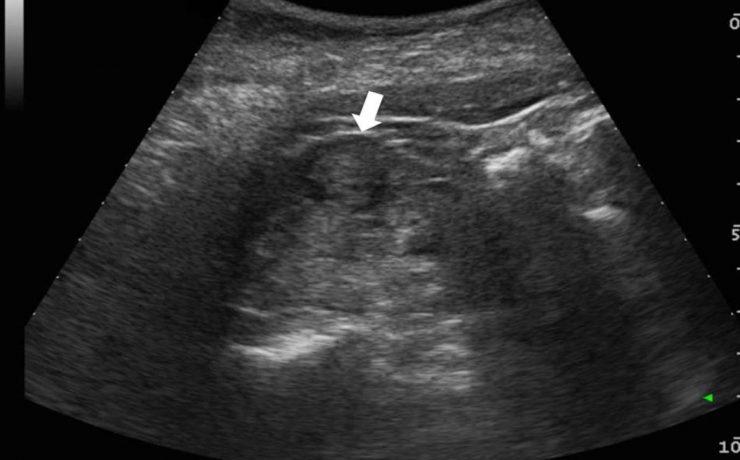

Caso clínico Se presenta un caso clínico de hematocervix diagnosticado por ultrasonografía en una paciente peri menopáusica sin antecedentes de patología cervical. Se discuten las causas de esta alteración, la utilidad del diagnóstico por ultrasonido, su tratamiento quirúrgico y su relación con patologías en otros órganos y sistemas. Introducción La